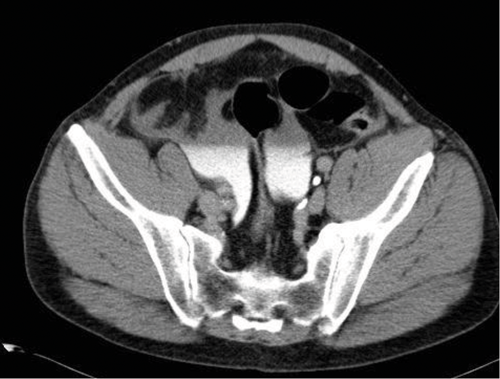

Case 4

- A CT urogram has been undertaken with contrast seen in both collecting systems. A CT cystogram was performed at the same time, with contrast instilled into the urinary bladder via existing Foley catheter. This allows assessment of both the upper tracts and the bladder to look for any injury following trauma. Contrast should be used at a concentration of 10% during CT cystogram, otherwise the contrast opacification will be too dense and make interpretation difficult.

- There is abnormal contrast opacification seen superiorly to the urinary bladder, within the peritoneal cavity.

- Findings are in keeping with an intraperitoneal bladder rupture. This is seen in approximately 15% of major bladder injuries and is usually caused by direct trauma to a distended bladder. The axial CT image demonstrates fluid, some of which has opacified with contrast, in the peritoneum.

- Surgical repair is required for intraperiteonal bladder rupture. Extraperitoneal bladder rupture is more common, accounting for 80-90% of cases, and is usually due to penetrating trauma or as a result of pelvic fractures. Treatment of an extraperitoneal bladder rupture is conservative, with a Foley catheter left in situ until the rupture heals.